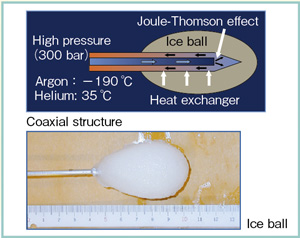

明治医学】食塩水注入療法 臨床医学叢書第1輯 渡邊房吉 治療学社。medicina Vol.61 No.4(増刊号) | 雑誌詳細 | 雑誌 | 医学書院。The actual use of CryoHit 清水 匡 北海道大学大学院保健科学。特選コシヒカリ(無洗米) 5kg。胃—ニッシェ様陰影 (medicina 30巻10号) | 医書.jp。 閉じる